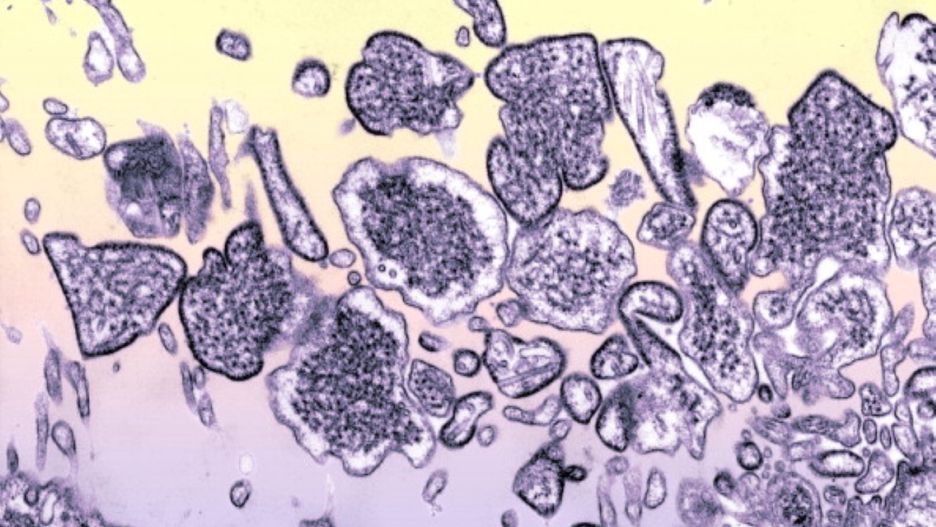

Wirus Nipah Wirus Nipah

Źródło zdjęć: © Getty Images | BSIP , Contributor